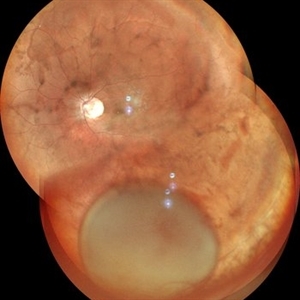

Dislocated Cataractous Lens Dislocated Cataractous LensFeb 11 2024 by Anjana Mirajkar, MS Ophthalmology A wide field image of LE of a 40 year old male showing inferior dislocation of crystalline lens which is cataractous in vitreous cavity. Photographer: Dr. Anjana Mirajkar -Retina Foundation, Ahmedabad Imaging device: Mirante-Nidek Condition/keywords: dislocated crystalline lens